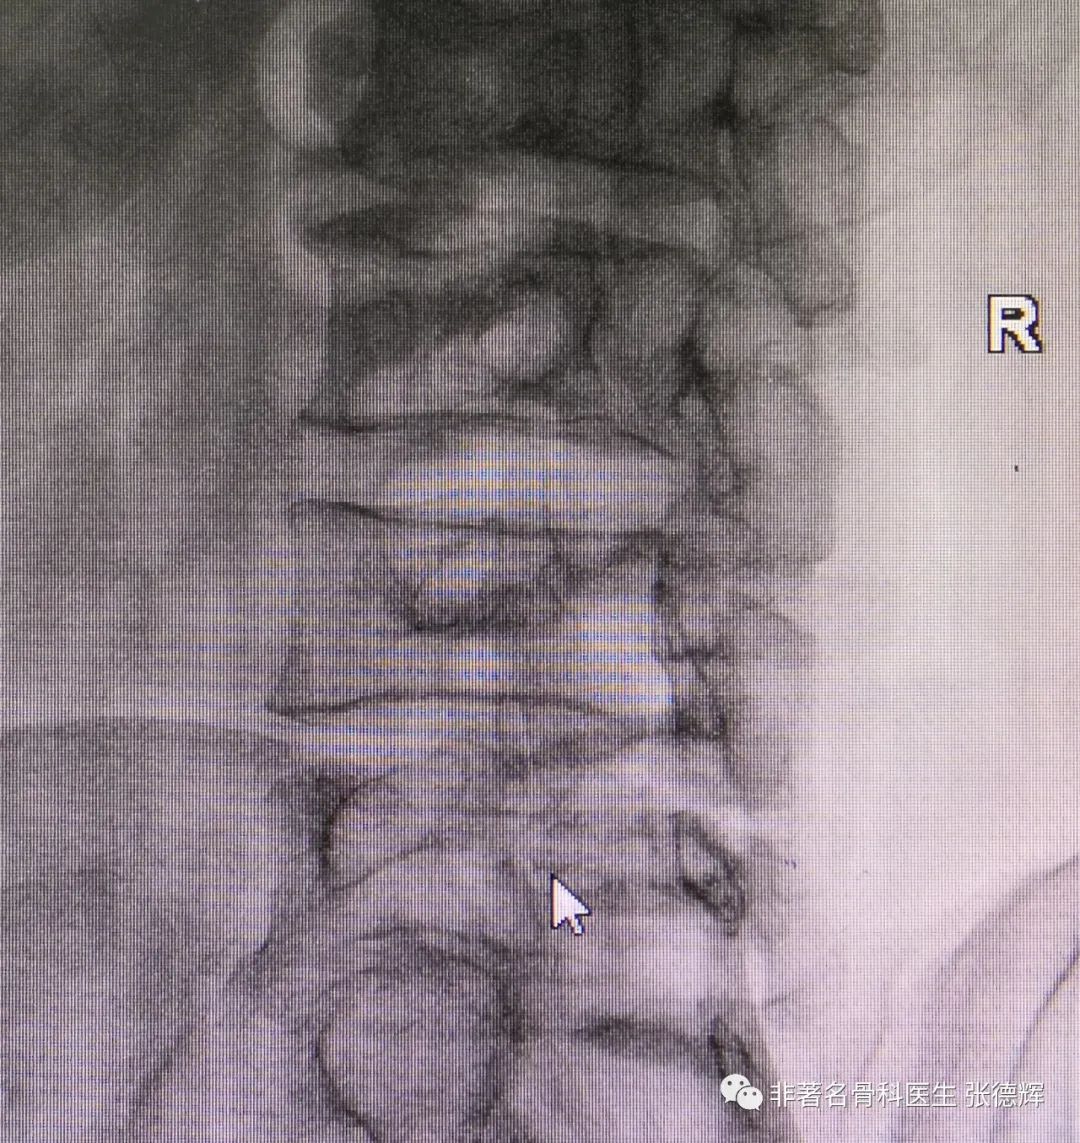

近期接诊一位腰椎峡部裂的患者,体重接近100公斤,腰腿痛近1年,严重时行走障碍,以下是影像检查资料。可以看到是明显的 腰5双侧峡部裂并轻度滑脱 。

腰椎双侧斜位片可见腰5双侧峡部骨质不连续

(“狗颈征”阳性,鼠标指示处)